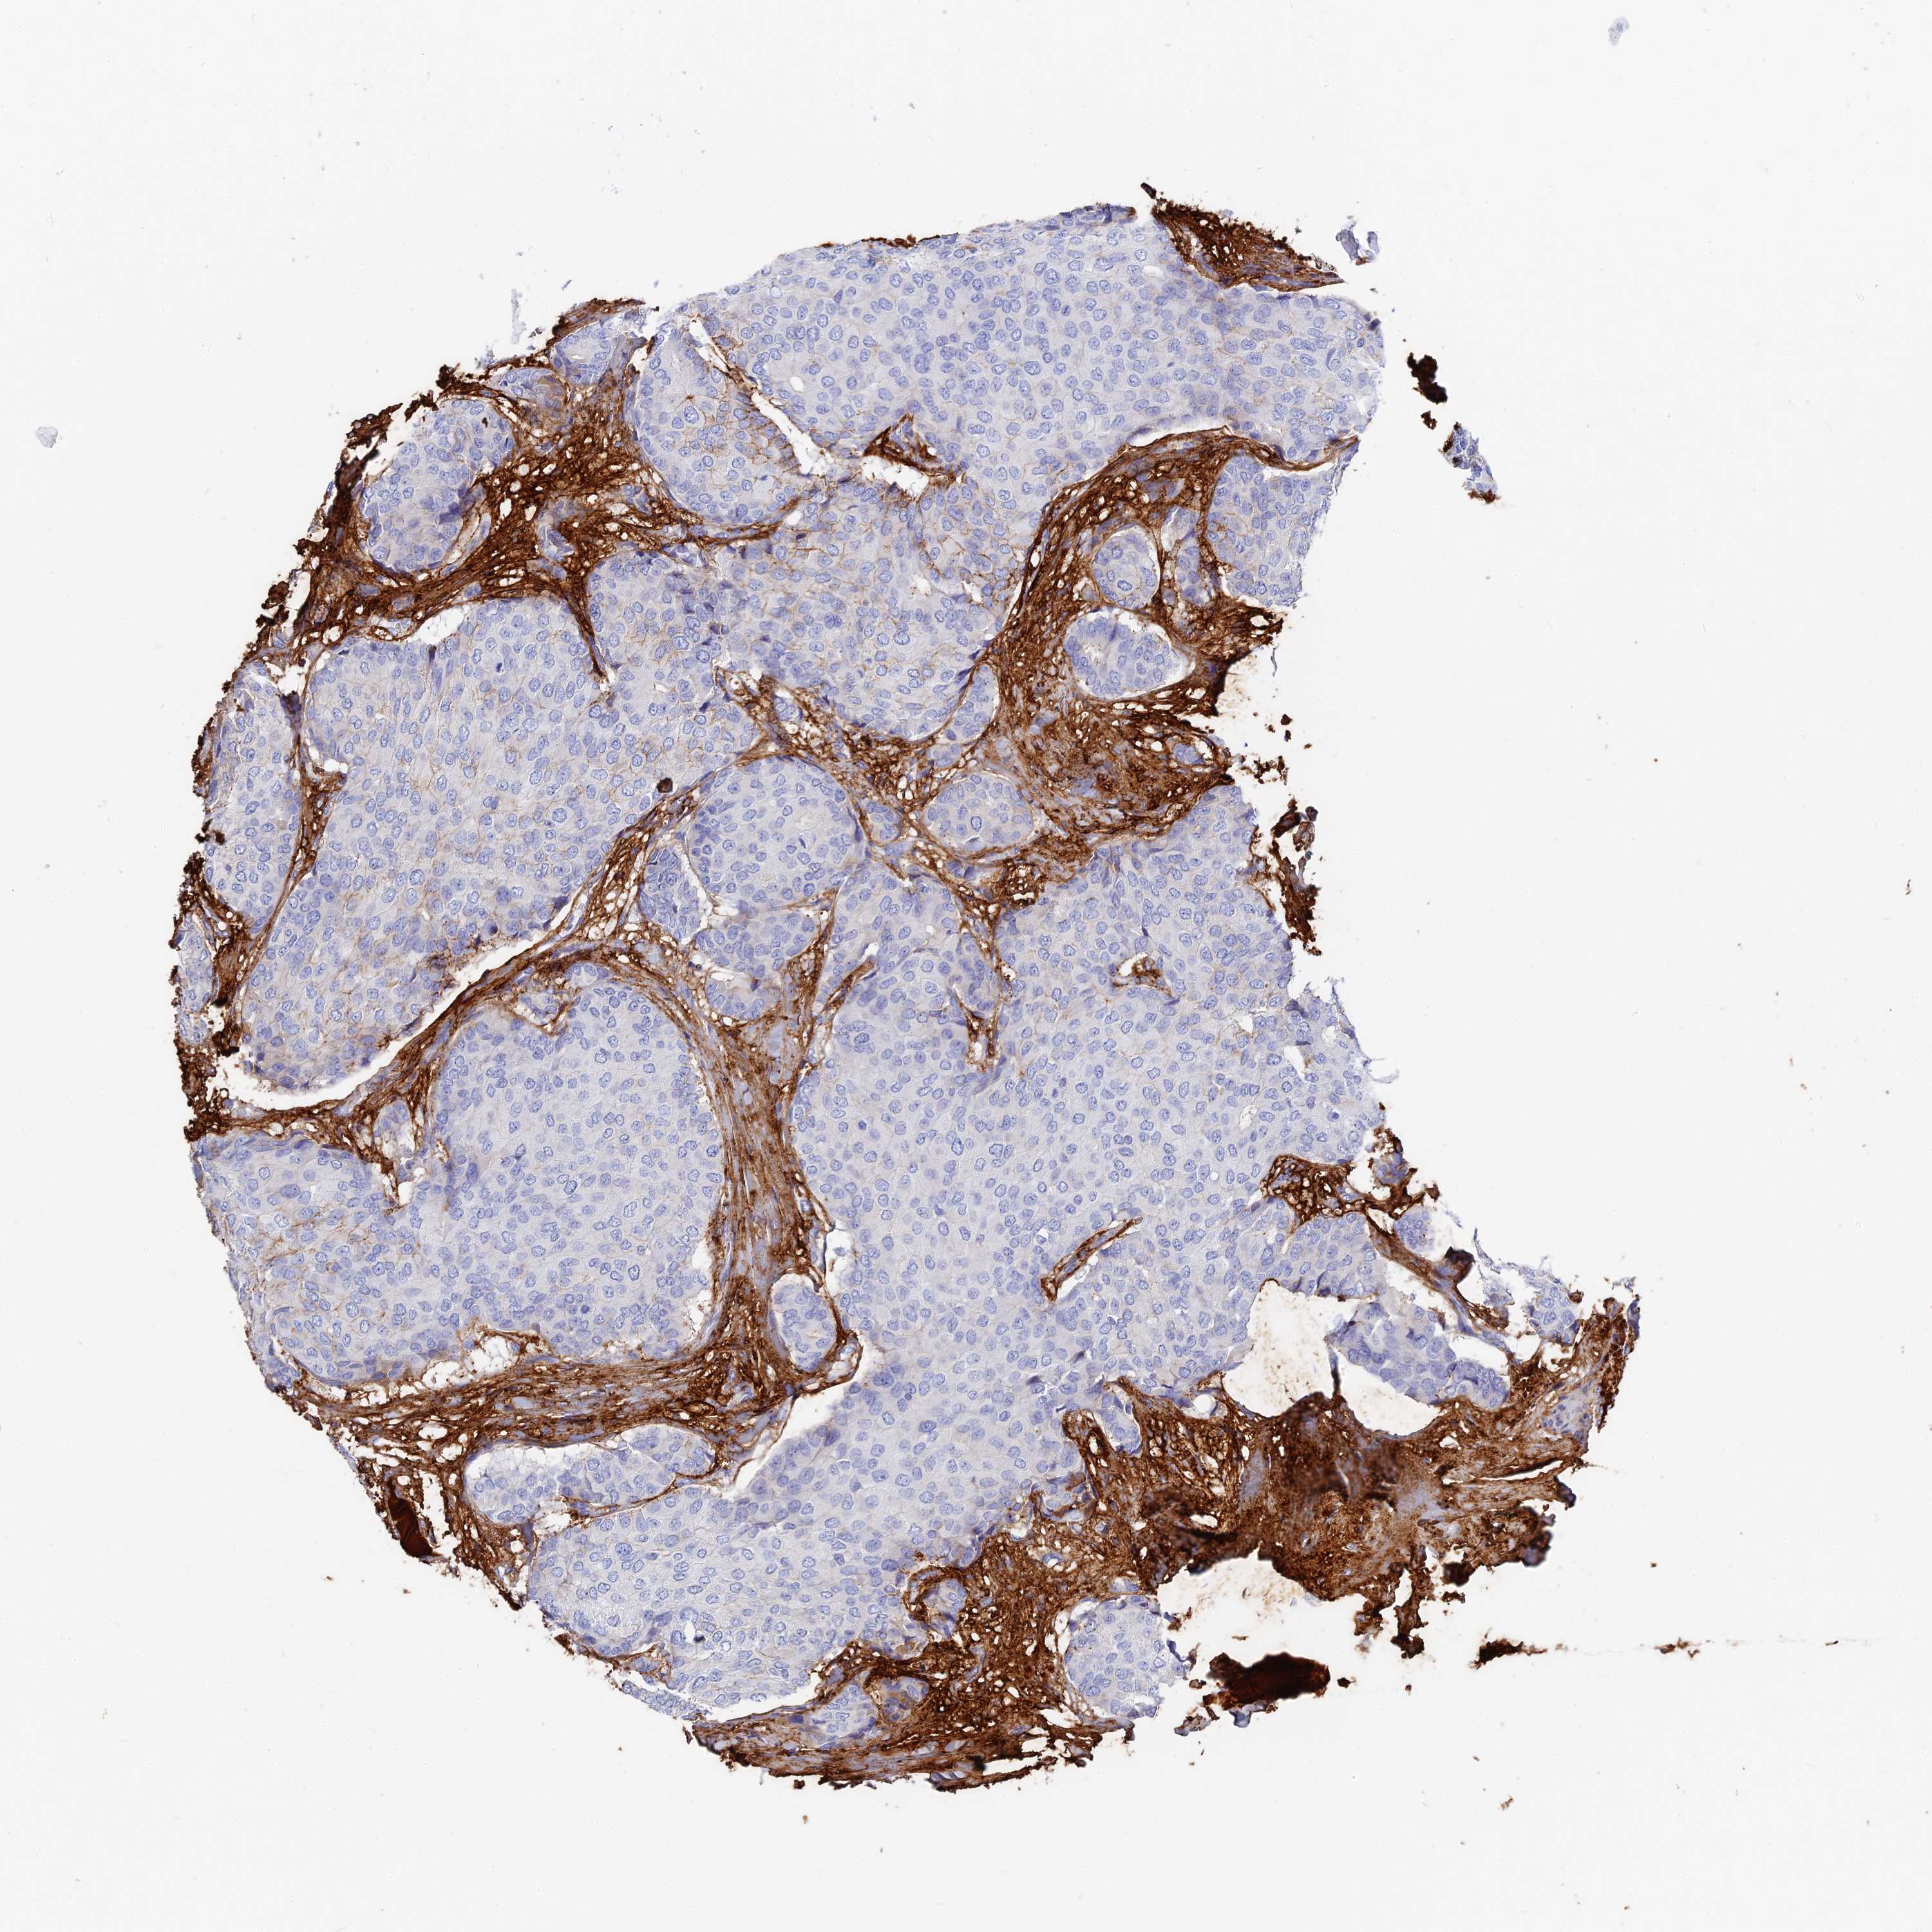

CANCER BREAST CANCER Show tissue menu

BRCA TCGA BRCA VALIDATION PROTEIN EXPRESSION